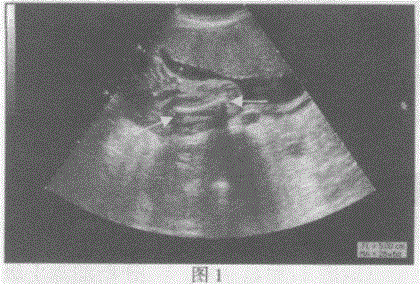

问题 请指出下图箭头所指的是胎儿哪一部位:

选项 A.图1:胎儿肱骨长径图2:面部 B.图1:胎儿胫骨长径图2:手 C.图1:胎儿股骨长径图2:脚 D.图1:胎儿桡骨长径图2:颈部

答案 C